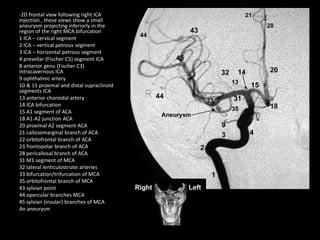

-2D frontal view following right ICA

injection , the appearance of the carotid

circulation is normal , Note the early

bifurcation of MCA (normal variant)

1 ICA – cervical segment

2 ICA – vertical petrous segment

3 ICA – horizontal petrous segment

4 presellar (Fischer C5) ICA

6 horizontal (Fischer C4) intracavernous

ICA

9 ophthalmic artery

10 & 11 proximal and distal supraclinoid

segment ICA

12 posterior communicating artery

13 anterior choroidal artery

14 internal carotid artery bifurcation

15 A1 segment of ACA

17 recurrent artery of Heubner

20 proximal A2 segment ACA

21 callosomarginal branch ACA

28 pericallosal branch of ACA

31 M1 segment of MCA

32 lateral lenticulostriate arteries

33 bifurcation/trifurcation of MCA

34 anterior temporal lobe branches of

MCA

35 orbitofrontal branch of MCA

43 sylvian point

44 opercular branches of MCA

45 sylvian (insular) branches of MCA